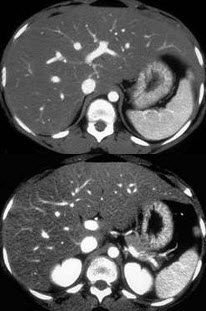

男,56岁,体型肥胖,有饮酒史30余年,CT检查见图,最可能的诊断是( )

A:脂肪肝

B:肝色素沉着症

C:肝硬化

D:肝癌

E:肝豆状核变性